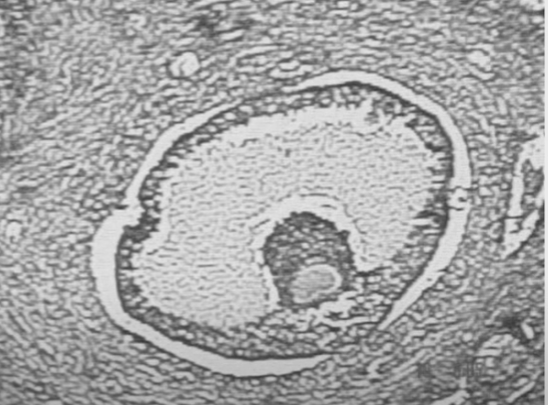

• Óvulo y folículo de Graaf

Óvulo y folículo de Graaf

Utilizando el microscopio de Leeuwenhoek, Regnerus de Graaf visualiza por primera vez un óvulo y un folículo que lleva su nombre.